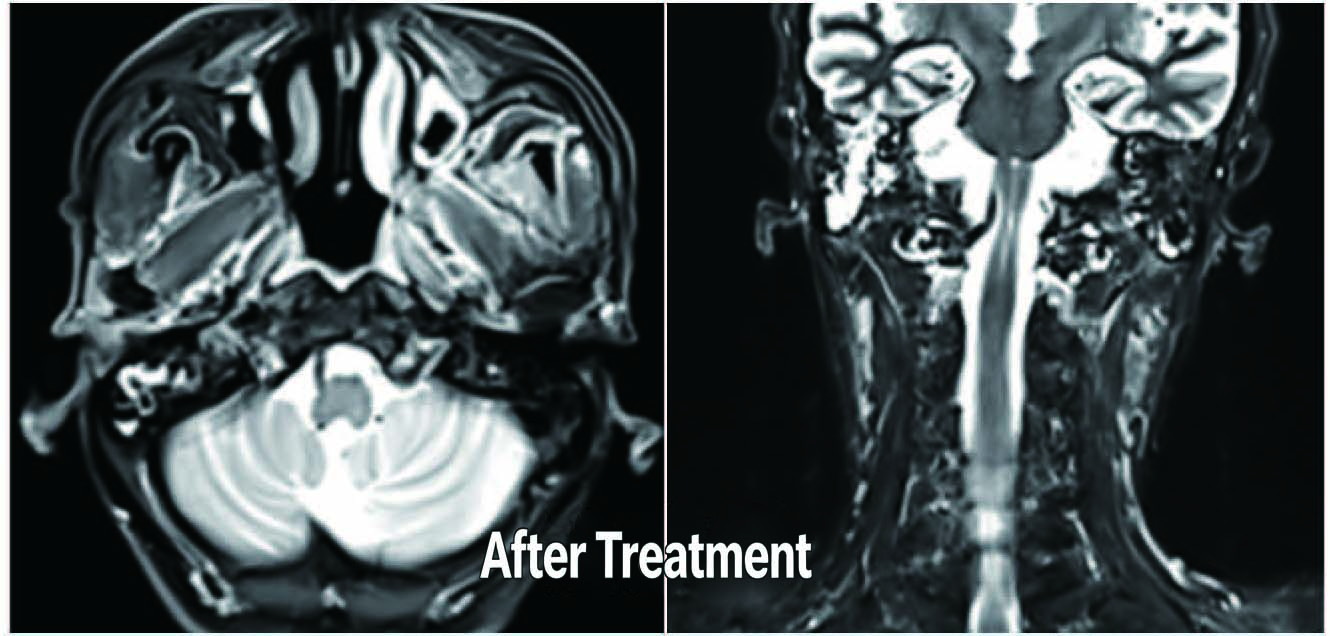

Before Treatment

After Treatment

Patient: Male, Elderly

Diagnosis: Lung cancer with brain metastases, accompanied by brain dysfunction, requiring wheelchair Observations:

Before Treatment: Severe peritumoral edema with elevated intracranial pressure

After 5 sessions of radiotherapy, tumor regression was observed.

Outcome: After treatment, there was a remarkable improvement in brain function, and the patient regained the ability to walk independently.